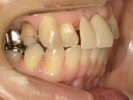

50代女性

治療前 |

治療中。仮歯。 左上の奥にインプラント埋入。 噛みあわせ治療を行いました |

治療後 全体の歯で食事がおいしくできるようになったと喜んでおられました。 |